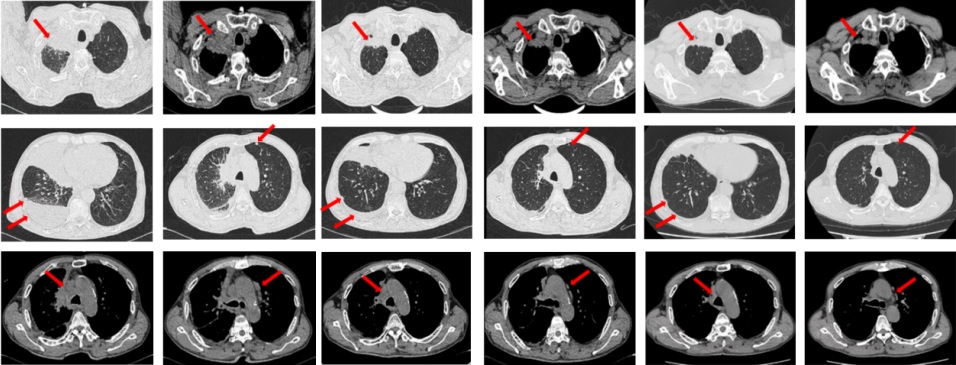

如图7所示,2021年7月复查评效PD。重新行右肺穿刺取得病理,提示腺癌。NGS组织基因检测:MET基因扩增(变异倍数)4.0倍。改行赛沃替尼联合奥希替尼治疗。治疗10日后突发一过性寒战伴低血压,不除外药物相关,对症治疗后好转。复查评效达PR,因患者无法耐受药物不良反应,改行奥希替尼联合克唑替尼治疗至今,定期复查,最佳评效PR,末次评效SD(2024年7月)。

图7:A.奥希替尼治疗后病情进展,右肺内病灶较前再次增大,同时右肺内新发转移灶;B.出现MET扩增后,奥希替尼联合MET-TKI治疗后肺内病灶较前明显缩小;C.当前方案治疗持续有效。

图8:第2例患者的整体诊治过程